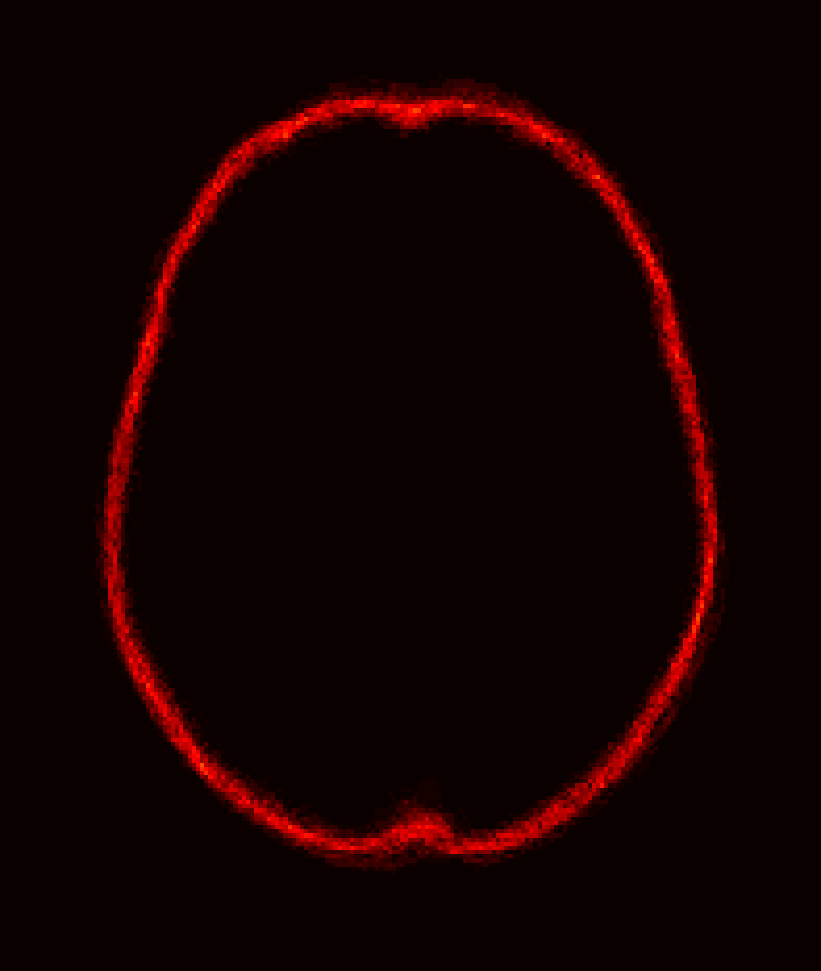

Fig. 1 shows example images from each dataset to illustrate image variability. IBSR and LPBA40 contain images from normal subjects and include large portions of the neck; BRATS has very low out-of-plane resolution; and the TBI dataset contains large pathologies and abnormal skulls.

Refer to caption

Figure 1: Illustration of image appearance variability on a selection of images from each (evaluation) database. From top to bottom: IBSR, LPBA40, BRATS and TBI.